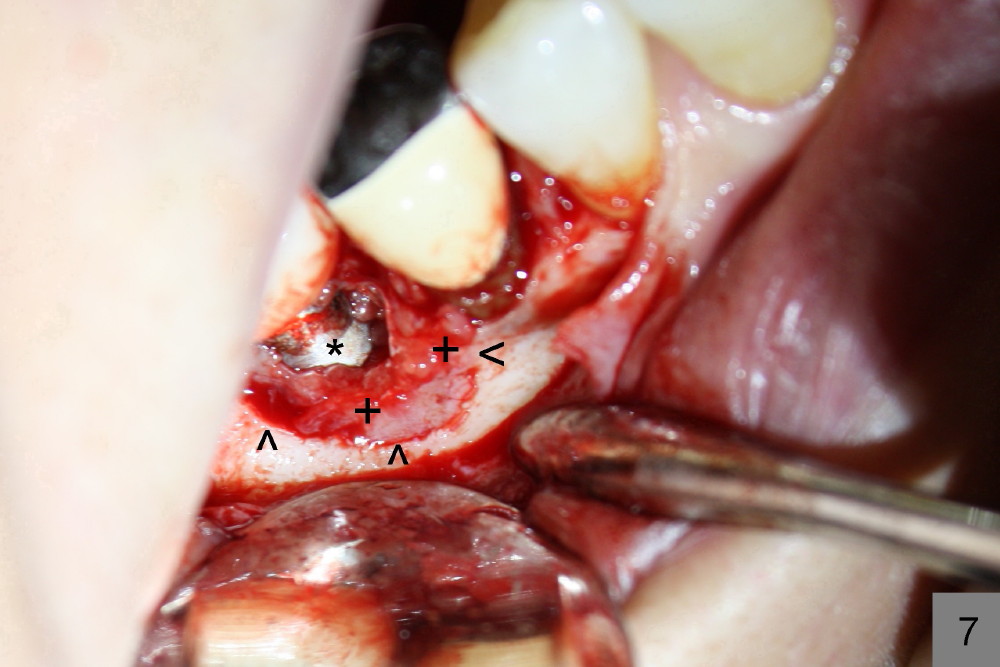

六十三岁台湾太太两年前右下第一磨牙准备做植牙,术前X光片显示缺牙区近中牙槽脊骨质好像有些特殊(图一箭头)。六乘十七毫米植牙(I)刚植入(图二,做了bone expansion),近中骨质好像又没有问题(箭头)。六个月后植牙近中骨质游离(图三箭头),除去骨片后,牙龈愈合,一个月后戴上牙冠(图四C),近中骨质仿佛没有异常。一年半后,病人突然回诊所,抱怨植牙周围流出臭味水,有些压痛。检查发现牙冠近中有个瘘道(图六箭头),下面好像有游离骨片,植牙牢靠,根尖片显示近中上部骨质稀疏(图五*),游离骨片(箭头)。翻开牙龈,除去相当大游离骨片,植牙粗糙面暴露(图七*,原有游离骨片所在地),除去炎性肉芽组织(+ +)后,植牙上部一两个螺纹暴露,箭头表示骨缺损边缘。反复用生理盐水冲洗,然后稀释四环素溶液冲洗,用探针和curet轻轻刮除植牙表面和螺纹菌斑,涂Straumann PrefGel,又用生理盐水冲洗,涂Endogain,植入Rocky Mountain Irradiated Allogenic Cancellous Bone and Marrow (图八*)。沐旭生医生认为植骨可能不管用,细菌很难清除,最好拔除植牙,植骨,然后再植牙。病人自己也意识到这个可能性,现在只有希望奇迹出现:缺损太大,不植骨身体可能无法修复。

沐旭生医生反馈:双氧水冲洗效果好,颊侧骨坏死可能原因钻洞产热,颊侧骨板太薄。如果伤口愈合,植牙可能暴露,重做牙冠盖住暴露那部分植牙表面。